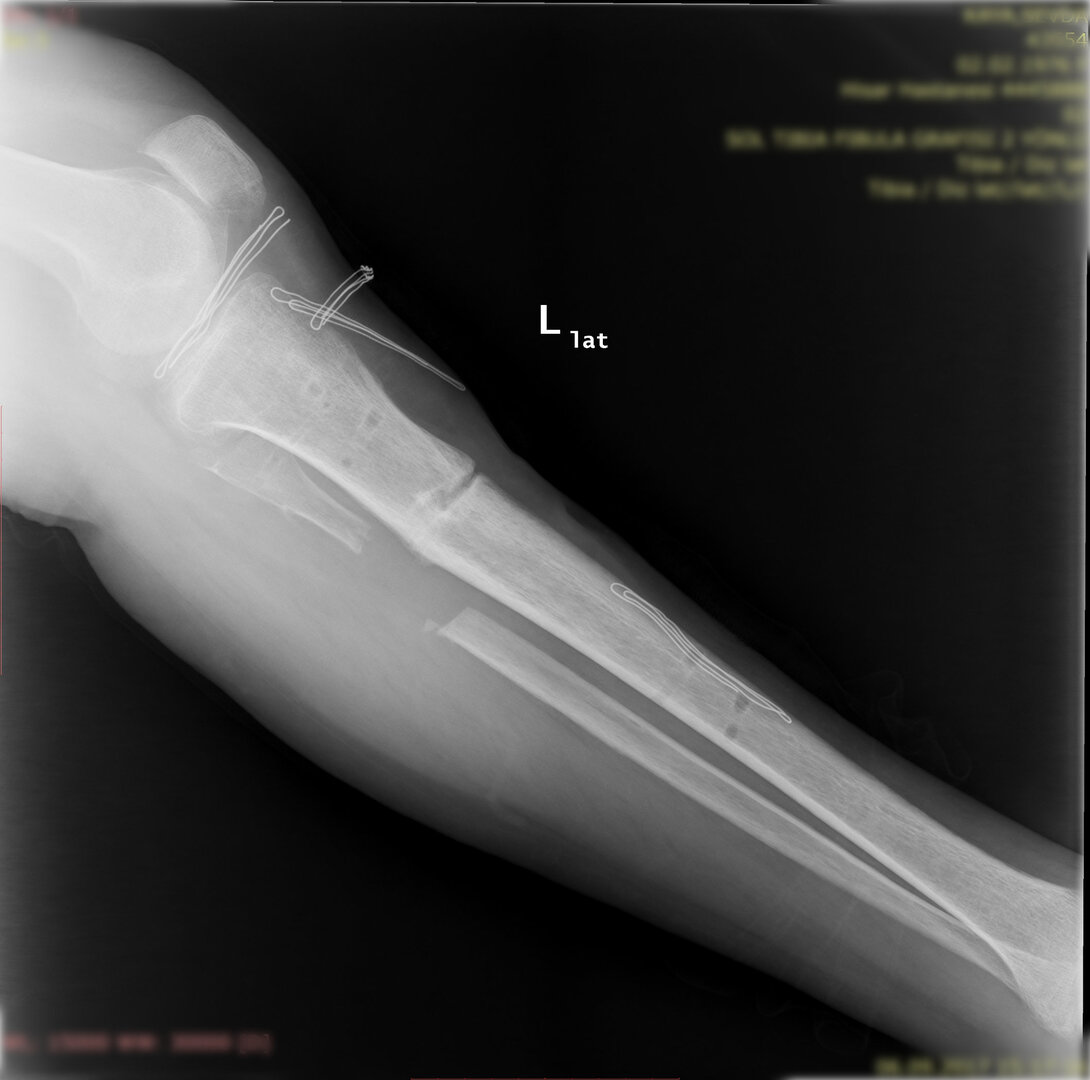

Deformitenin yeri ve miktarına bağlı olarak bilgisayar destekli sirküler eksternal fiksatör ile tedrici düzeltme yapılabilir. Bu sistemin avantajı düzeltme esnasında sistemle oynayarak yeni düzenlemeler yapmanıza izin vermesidir.

Diğer bir yöntem akut olarak düzeltme yöntemidir. Bu yöntemde kemiğe uygulanılan tespit yöntemi plak-vida kombinasyonu olabileceği gibi bir intramedüller çivi de olabilir.

Bu ameliyat öncesi bir deformite analizi yapılıp hangi kemikte, normalden ne kadar sapma olduğu tespit edilir. Daha sonra bu kemiğe yine ostetomi yapılarak bu anormal sapma düzeltilir.  Bu düzeltme plak-vida veya intramedüller çivi ile akut olarak düzeltilebileceği gibi bilgisayar destekli sirküler eksternal fiksatör ile tedrici olarak ta yapılabilir. Hangi yöntemin hangi hasta için uygun olacağına hasta özelinde karar veriyoruz, ne tür cerrahi tedavi olması gerektiğini danışabilirsiniz.

Büyütmek için üzerine tıklayınız.